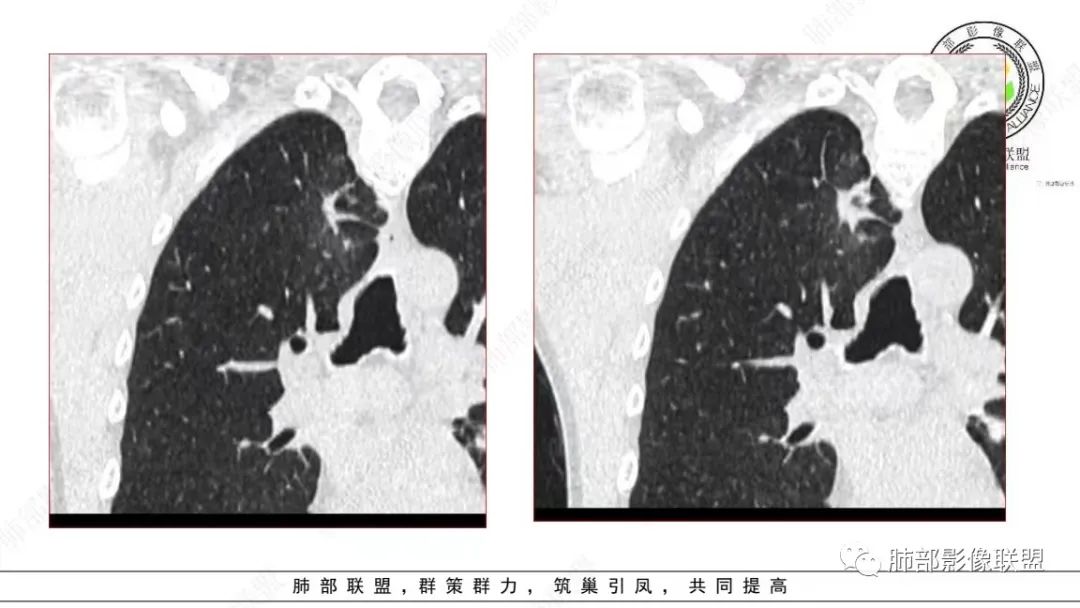

细支气管腺瘤的病理要点中,很重要的一点就是双层细胞。返回来看影像,这个病变还是很有特点的,诊断结核确实有点不合适。一点点的看。

:

仔细看,里面是有低密度的。平扫CT值也很低,才16HU。

增强也很有特点。这些低密度,是有延迟强化特点的。

平扫低密度,就这个病变而言,我们最容易想到的:干酪性坏死、黏液。而延迟强化。所以这个病变是不符合干酪性坏死的表现的。很多平直凹陷的地方,与胸膜宽基底接触,是否存在胸膜牵拉不详,需重建看看。说明这个病变是有收缩力的。里面含有一部分纤维。当然,含有纤维的,肿瘤的肌成纤维可以,上皮间质转换可以,慢性炎也可以,好多病变里面可以有纤维。干酪样坏死,是不会强化的。延迟强化,肉芽肿可以,纤维比较多的或者黏液多的也可以。

还是和病变成分有关。在肿瘤当中,或者上皮间质转换比较明显等,可以有不同的强化方式。当然也可以表现为延迟强化,可以动脉期明显强化。和肿瘤的具体类型,以及具体病变的病理成分有关。多层面观察,病变是明确有细支气管进入的,而且明确的有铸型的低密度粘液栓。